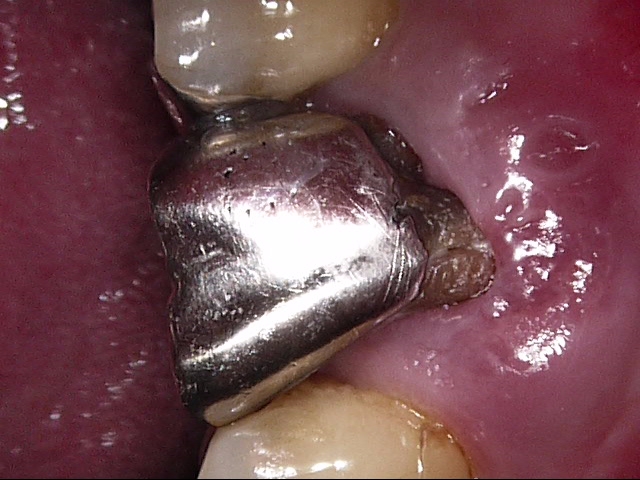

実際のケースを見てみましょう。

金属のメタルコアを除去して、ファイバーポストに置き換え、歯根破折のリスクを軽減したケース↓ 3本の歯にそれぞれメタルコアが入っています。

メタルコアを除去しました↓